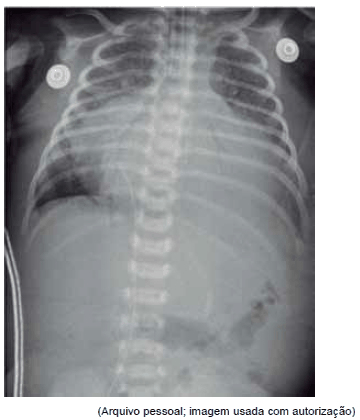

Paciente foi transferido de urgência em vaga zero de UBS para pronto-socorro cardiológico sem história de cardiopatia congênita prévia. Mãe refere que nasceu sem intercorrências, de parto normal, e teve alta no segundo dia de vida. Notou que sua criança tinha dificuldades às mamadas e ficava roxo aos esforços. Após exame físico e cuidados imediatos de intubação orotraqueal, cateter venoso central e sonda nasogástrica, foram feitos os seguintes exames:

Qual é o diagnóstico mais provável?